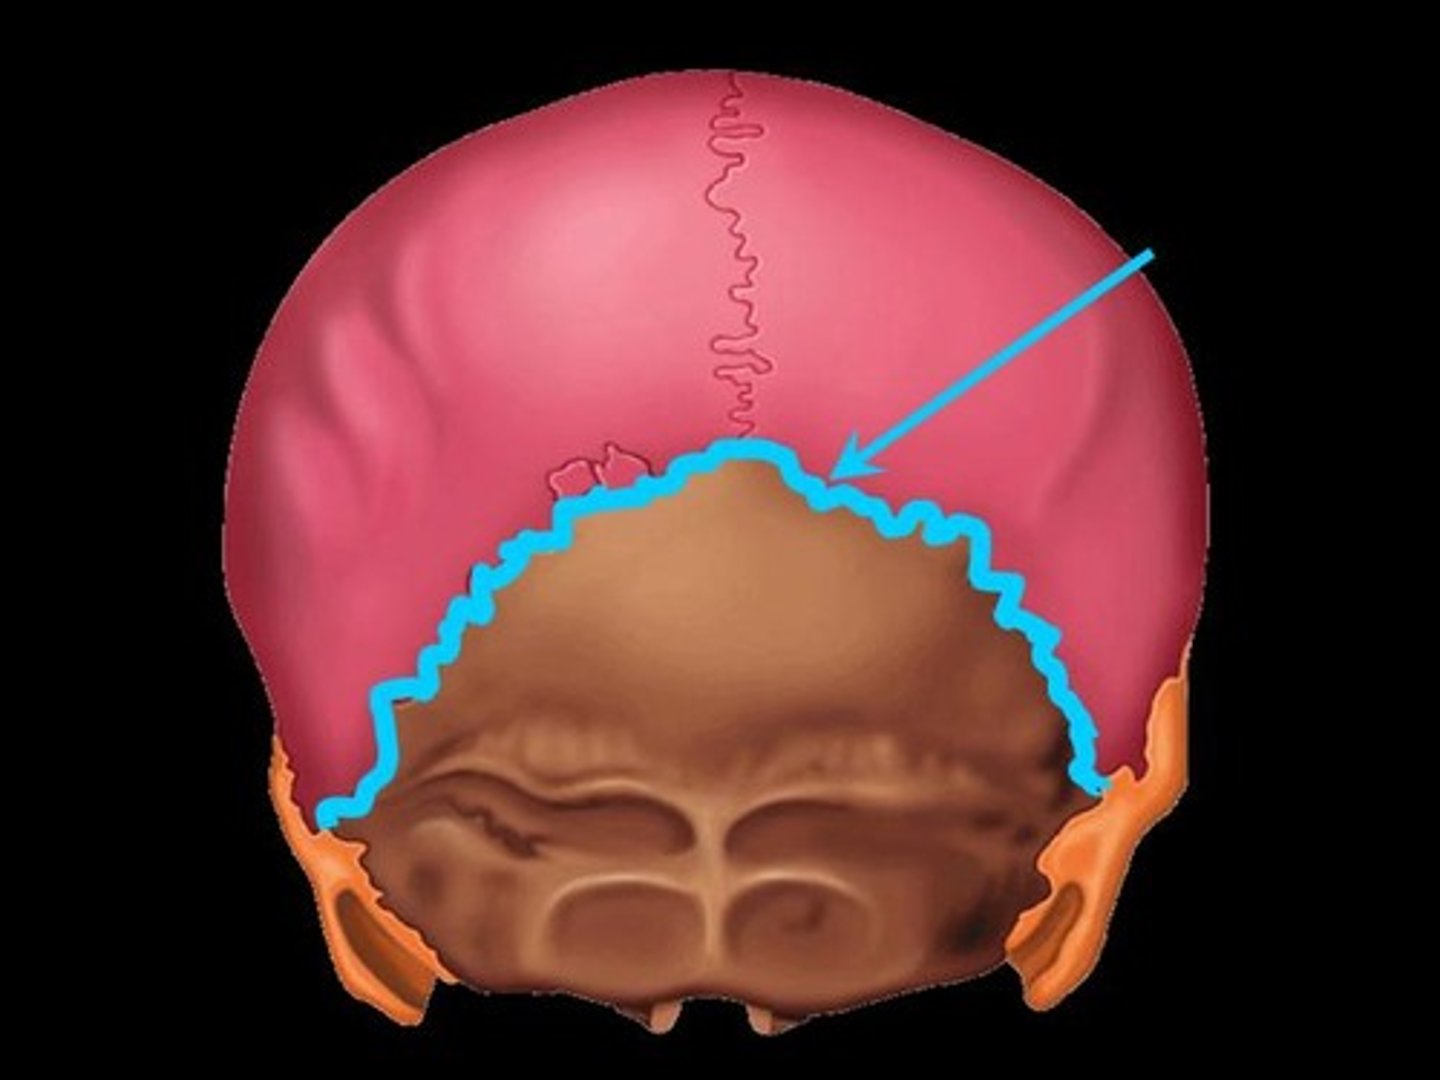

lambdoidal suture

asterion